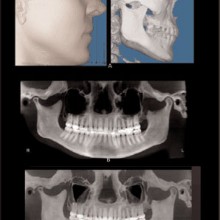

MAXIMUM INTENSITY PROJECTION (MIP) can be used to highlight features. The anatomic features associated with the brightest pixel or voxel intensity are projected on the display screen. This method creates a high-contrast image, but the brighter pixels/voxels may mask or superimpose over less-bright pixels, thus potentially hiding important anatomic features. MIP projections of a CBCT volume or slab (right or left sides) may be a useful method to produce constructed panoramic and cephalometric images for orthodontic purposes (Figure 3). Shaded surface Rendering (SSR) is useful for high-contrast imaging such as bone. SSR techniques allow the operator to set a pixel or voxel intensity threshold that excludes structures lower than the selected threshold, and renders all structures greater than the selected threshold (Figure 3). SSR creates a three-dimensional model that can be rotated as an object to be viewed from any angle. When the tissue contrast is not high, then the selected threshold may not perfectly render the desired anatomy. Volume rendering (VR) also creates a three-dimensional model using no

pixel/voxel threshold for data exclusion (Figure 4). The entire volume is always loaded but tissues are interactively grouped by voxel intensity, and each group can be assigned with a color and transparency value prior to projecting the volume onto the viewing monitor. The operator can rotate the VR model and change the opacity levels, thus providing the sense of peeling away tissues layer by layer. VR is a good way to visually understand the anatomic relationships between structures, and can be used effectively for treatment planning and as a communication tool.

ORTHODONTIC RECORDS: The greatest recent innovation has been the inclusion of the spatially true-size three-dimensional digital image data into the orthodontic records. Ultimately the three-dimensional records will replace the two-dimensional records. The current generation cone beam CT promises to produce, in a single scan, enough information to eliminate the need for conventional panoramic, occlusal, cephalometric, selected periapical, and tempormandibular-joint tomographic studies and possibly plaster dental models. The CBCT data will be superior to that gained from the compiled series of two-dimensional images, and the absorbed dose will be less.

With the traditional two-dimensional dental-imaging series some areas of anatomy are poorly visualized. These three-dimensional scans can give valuable information about other areas of the dentition such as the position of the upper incisor roots relative to the lingual cortical border of the palate to plan retraction, the amount of bone available in the posterior maxilla available for distalization, the amount of bone lateral to the maxillary buccal segments available for dental rather than skeletal expansion, airway information on the pharynx and nasal passages, upper root proximity to the maxillary sinus, the three-dimensional extent of an atrophied alveolar ridge, or the position of the lower incisor roots in bone. These scans also allow three-dimensional visualization of bony defects and supernumerary teeth in patients with cleft lip and/or palate. Additionally, axially corrected tomograms of the temporomandibular joints can be obtained from the same scan. The ability to visualize an axially corrected view of the temporomandibular joints with the teeth in occlusion on the same reconstructed section is one significant advantage of the volume scan. Therefore, there is substantial “value-added” imaging benefits to these scans for complicated orthodontic patients.